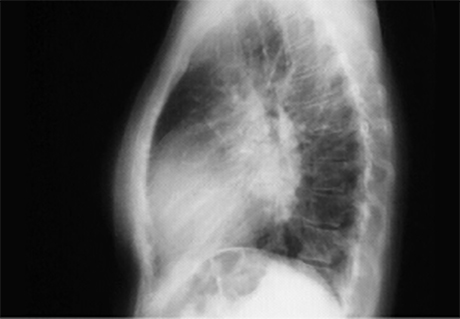

Lat

is greater than 50%, reflecting cardiomegaly. In the lateral view,

left atrial enlargement

is further reflected by the prominent posterior left atrial shadow. Right ventricular enlargement is best seen in this view and is manifested by

obliteration of the retrosternal air space.